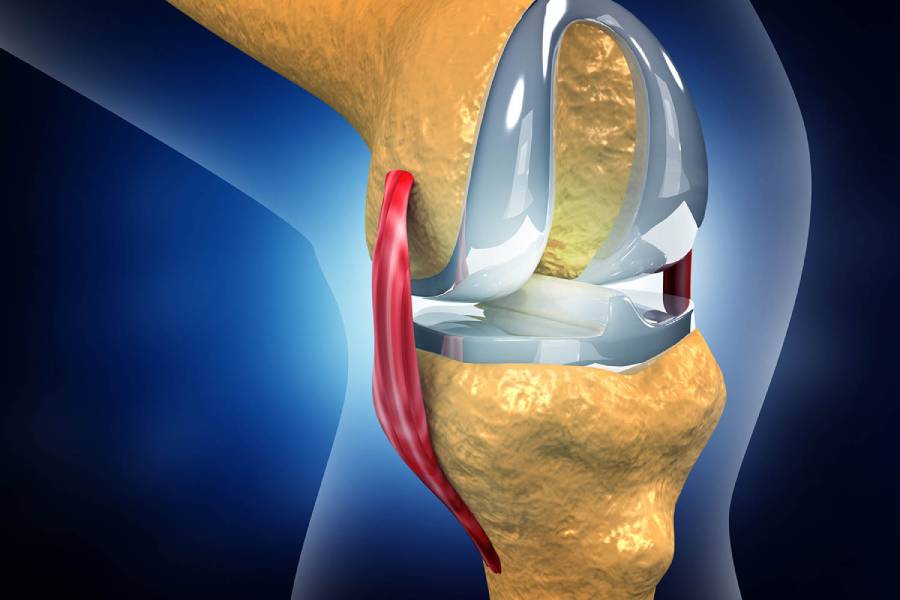

In Total Joint Replacement Surgery, the entire joint surface is replaced with an artificial implant. It's commonly performed for severe arthritis or trauma involving the hip, knee, or shoulder.

Knee joint replacement is one of the most frequently performed orthopaedic surgeries. It replaces the worn-out surfaces of the knee with metal and plastic components, providing pain relief and stability.

Each surgery is customised according to the patient’s anatomy, lifestyle, and activity level. At OrthoPatna, Dr. Ashwini Gaurav performs all these procedures using advanced techniques and precision-guided equipment to ensure optimal outcomes.